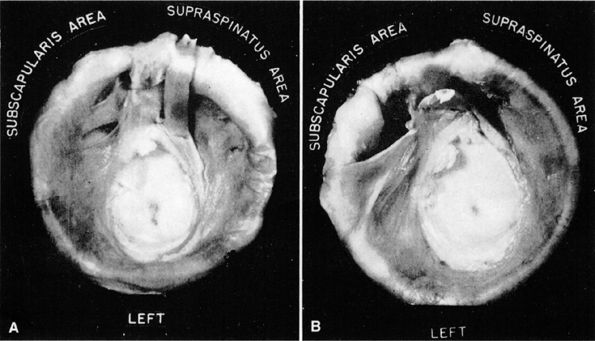

muscle. Glenohumeral joint version or humeral retroversion projects the axis of the humeral head joint surfaces 25° to 40° from the coronal plane, whereas the glenoid surface is retroverted 4° to 12° with respect to the scapula.46 The glenoid labrum, wedge-shaped in cross-section, is a ring of fibrous tissue with transitional fibrocartilage attached to the margin of the glenoid cavity.47 Labral tissue deepens the depression of the glenoid fossa and enlarges the glenohumeral socket contact area (Figs. 8.58 and 8.59).

FIGURE 8.59 ● The scapular component of a disarticulated shoulder joint. The relations and internal features of the joint are seen.